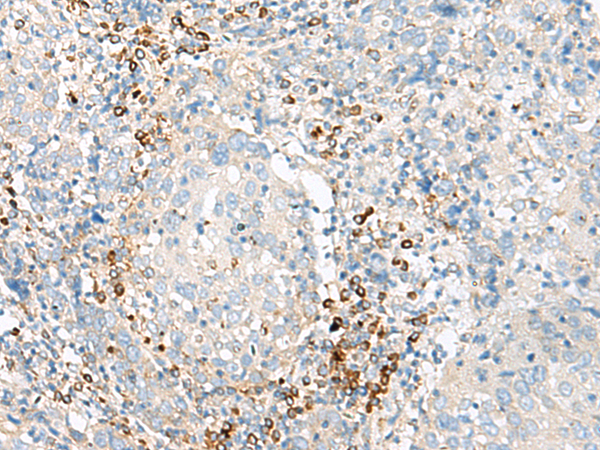

分类: 科研抗体货号: P43586别名: GPCR; PGR7; GALR4; GALRL; GPCR-2037应用: IHC反应种属: Human